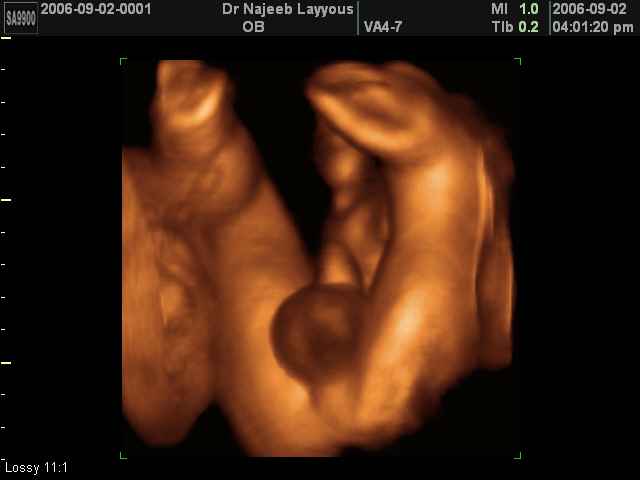

- Fetal Behavior Ultrasound Photos